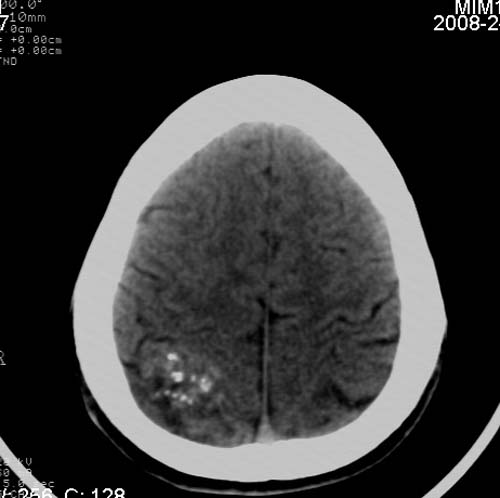

男,17岁,3天前与人斗殴,自述头痛、头晕。无恶心、呕吐,无阳性体征,一般情况良好。

病灶以钙化为主,无明显占位效应,病灶周围无水肿,这种情况应该是脑血管畸形,最多见的是动静脉畸形,其次是海绵状血管瘤.

病人较年轻,有头疼、头晕症状,动静脉畸形可能性大。